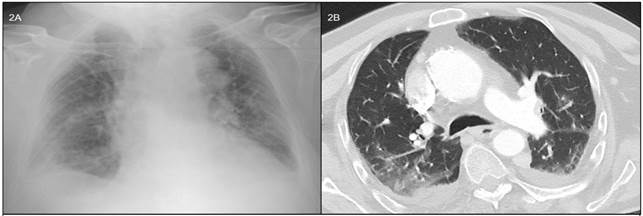

Varón de 71 años con deterioro cognitivo secundario a meningitis durante la infancia y portador de sonda vesical por hipertrofia benigna de próstata y episodios repetidos de retención urinaria; presenta un cuadro de 5 días de evolución caracterizado por malestar general, febrícula, tos y lesiones dérmicas pruriginosas que se iniciaron en tronco y se han extendido sobre toda la superficie corporal. Acude a Urgencias por empeoramiento de la erupción en las últimas 24 horas, acompañado de pico febril de 38,5 ºC y aparición de disnea rápidamente progresiva que se ha hecho de mínimos esfuerzos. Había sido valorado 3 días antes, cuando aparecieron las primeras lesiones dérmicas y se le indicó deflazacort y cetirizina. A la exploración física, se encontraba hemodinámicamente estable con fiebre de 38 ºC y taquipnea, sin uso de musculatura accesoria y manteniendo una saturación basal de oxígeno del 86 %. Presentaba un exantema generalizado con lesiones en distintos estadios evolutivos, incluyendo máculas, pápulas, vesículas y pústulas que afectaban palmas, plantas y mucosa oral (Figura 1). Los ruidos cardiacos eran rítmicos, aunque ligeramente taquicárdicos. El murmullo vesicular se encontraba conservado, sin ruidos añadidos. El resto de la exploración era normal. Con respecto a las pruebas complementarias, en el hemograma destacaba una ligera trombopenia de 119.000 sin leucocitosis ni anemia. Además, un discreto aumento de AST de 58 UI/l con glucosa, función renal, iones y resto de perfil hepático normal. La gasometría arterial basal mostraba datos de insuficiencia respiratoria parcial con pO2 de 58 y la radiografía de tórax un patrón intersticial bilateral (Figura 2A). Se iniciaron oxigenoterapia, fluidoterapia y aciclovir intravenoso. Se decidió ingreso en planta, donde se confirmó la sospecha diagnóstica al obtenerse Ig M positiva para varicela-zoster, habiéndose descartado otros patógenos respiratorios como Chlamydia pneumoniae, Mycoplasma pneumoniae, Coxiella burnetti, neumococo o legionela. Se solicitó TAC torácico que confirmó un infiltrado intersticial bilateral en vidrio deslustrado en relación con proceso infeccioso agudo y compatible con neumonía por varicela (Figura 2B). La evolución clínica fue favorable, con desaparición de la fiebre y la insuficiencia respiratoria tras 4 días de tratamiento. Posteriormente, al sexto día de ingreso se objetivó la normalización de las alteraciones analíticas. El paciente completó una semana de tratamiento intravenoso con aciclovir y fue dado de alta sin incidencias.

La neumonía por varicela suele presentar un curso insidioso con desarrollo de disnea, tos y dolor torácico entre 1 a 6 días después de la aparición de las lesiones cutáneas4; en algunos casos puede evolucionar en pocas horas hacia insuficiencia respiratoria aguda grave6 con necesidad de soporte ventilatorio e ingreso en unidad de cuidados intensivos. La radiografía de tórax suele mostrar infiltrados bilaterales difusos de predominio intersticial que afectan principalmente a las bases, la región perihiliar, o ambas, pudiendo asociar un componente micronodular al inicio del cuadro3,4. Tiene una mortalidad global de entre el 10 y el 30 % en adultos inmunocompetentes3-6, que aumenta hasta 50 % en pacientes inmunodeprimidos4; sin embargo, está disminuyendo en los últimos años probablemente debido al tratamiento antivírico precoz y a las adecuadas medidas de soporte6. En los casos de enfermedad diseminada, como neumonía, encefalitis o hepatitis, se recomienda aciclovir intravenoso a dosis de 10 a 15 mg/kg cada 8 horas durante 7-10 días3,4. En los casos de neumonía por varicela se ha demostrado que, si se administra precozmente, disminuye la fiebre y la taquipnea, obteniéndose una mejoría en la oxigenación6, así como una recuperación más rápida de la cifra de plaquetas5.